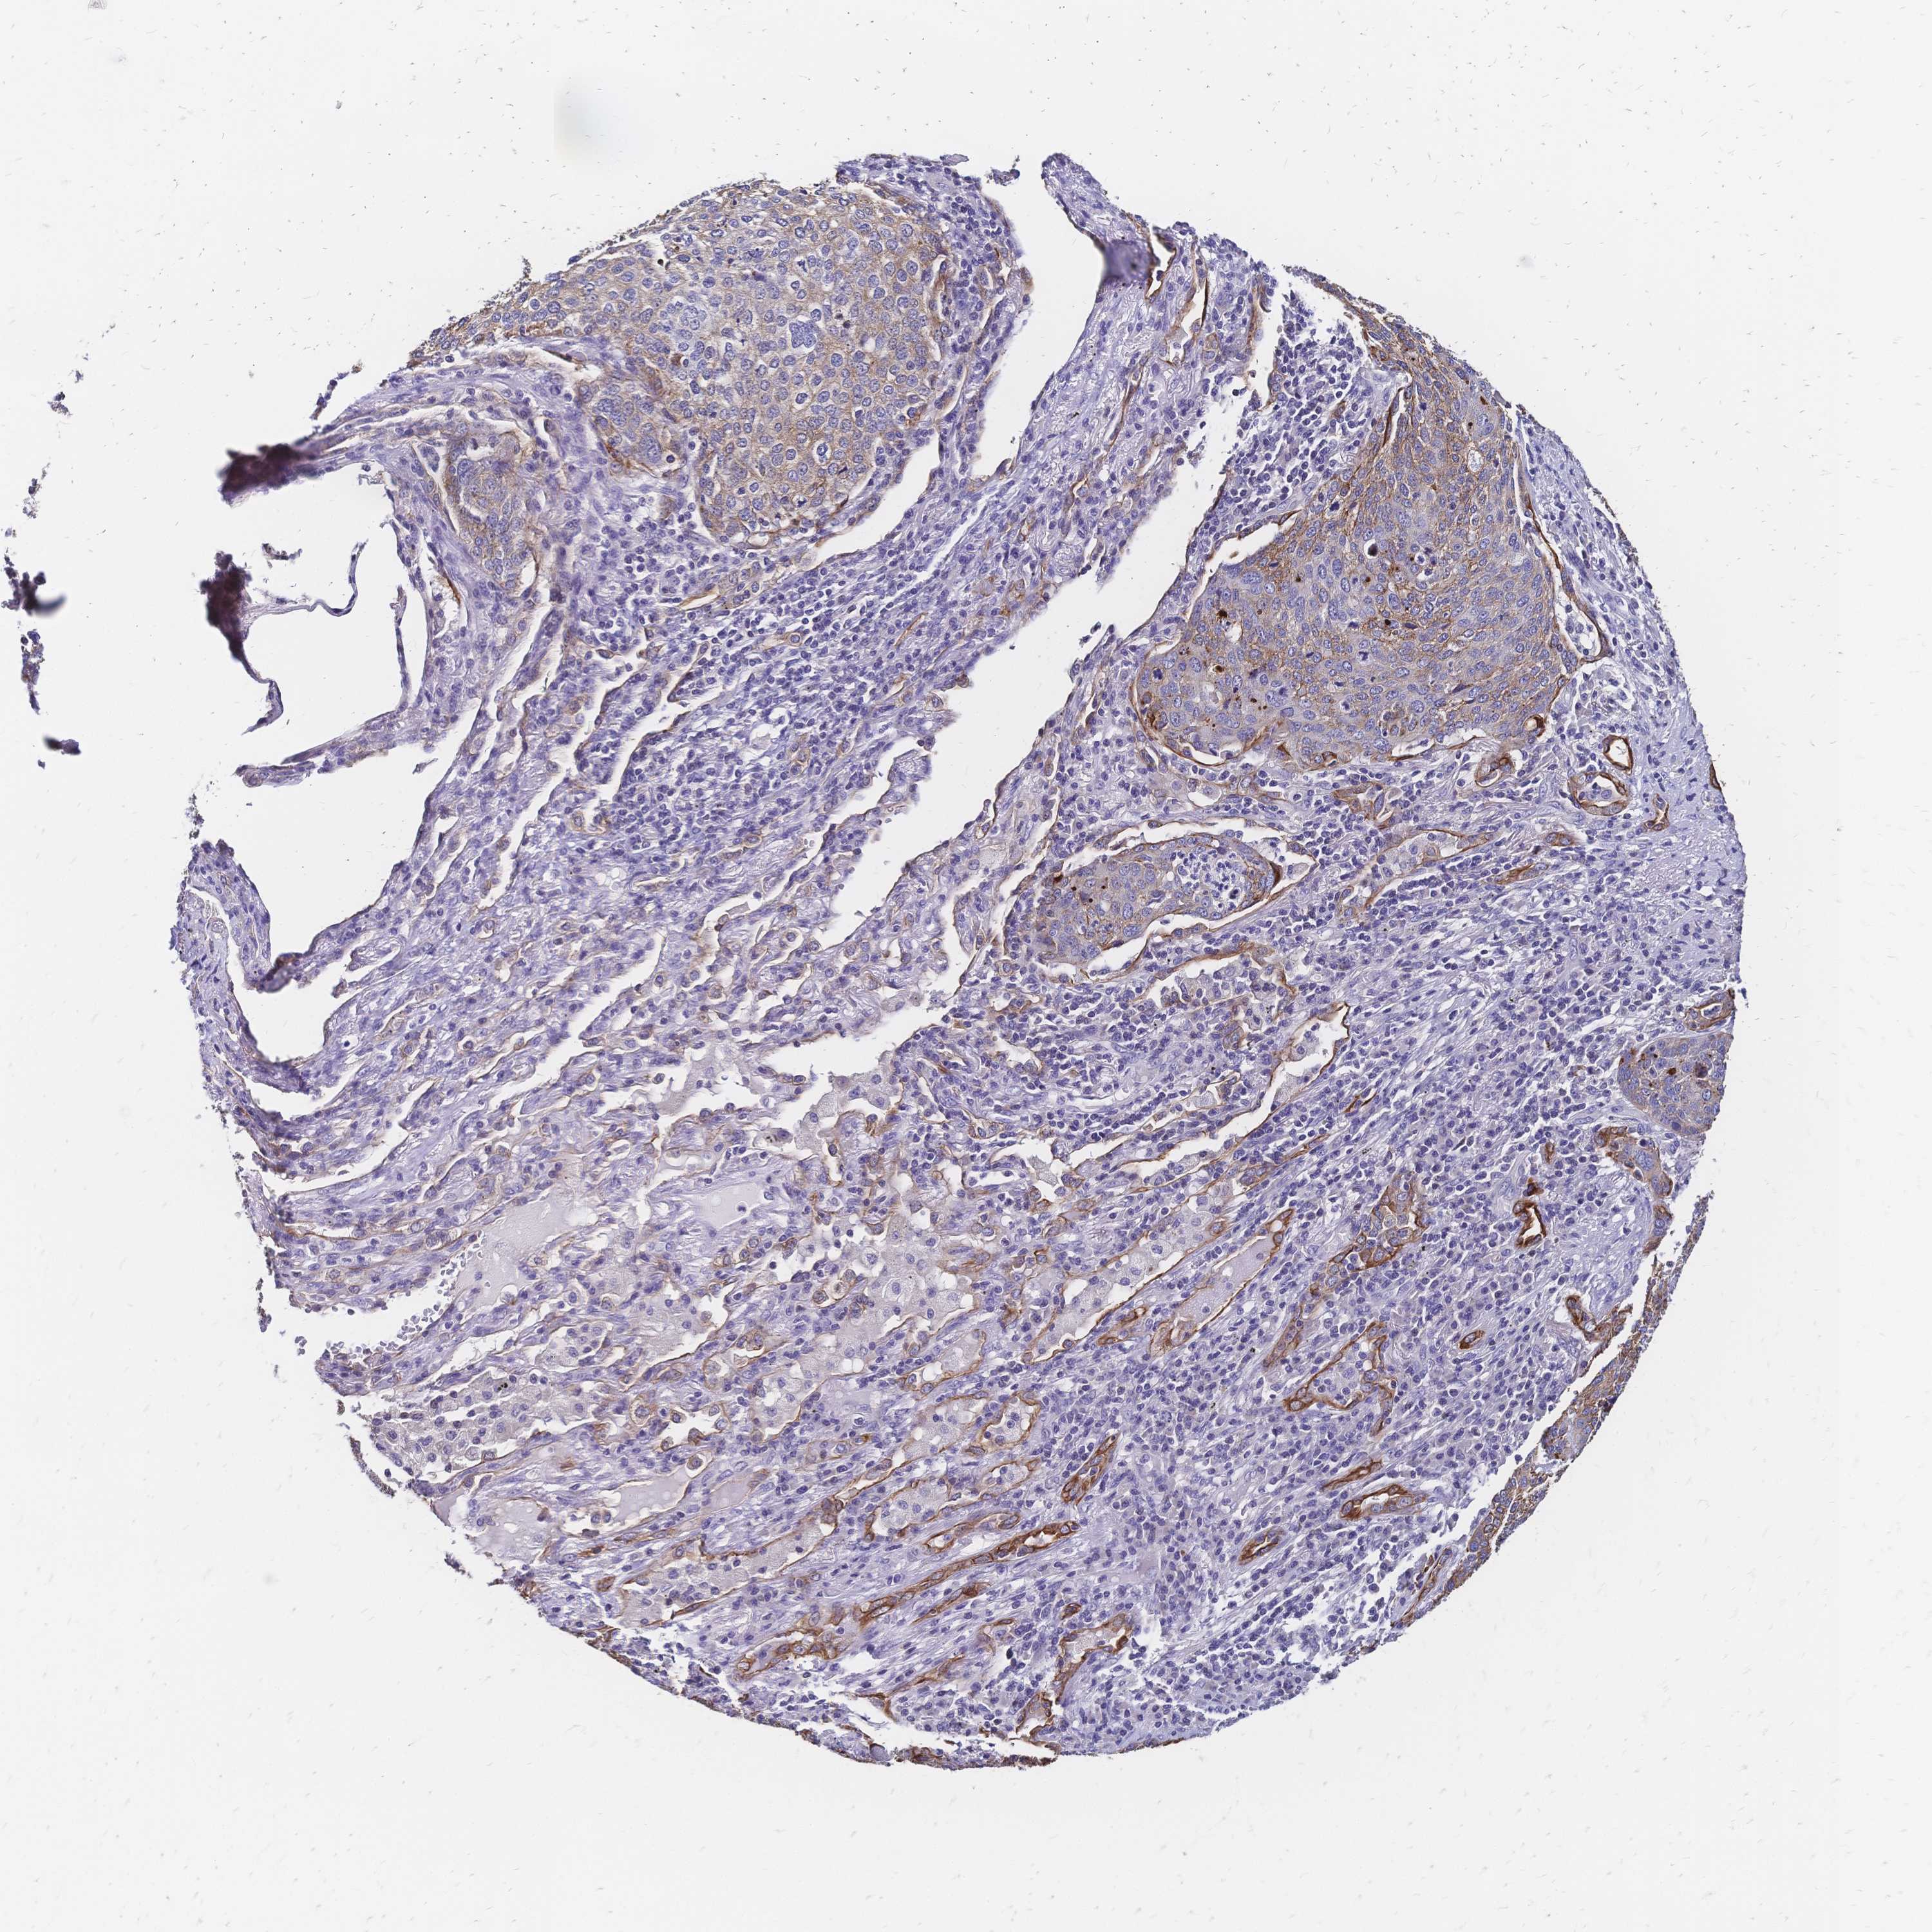

CANCER LUNG CANCER Show tissue menu

Lung cancer

Human cancer

Lung adenocarcinoma

LUNG ADENOCARCINOMA (TCGA) - Interactive survival scatter ploti

The Survival Scatter plot shows the clinical status (i.e. dead or alive) for all individuals in the patient cohort, based on the same data that underlies the corresponding Kaplan-Meier plots. Patients that are alive at last time for follow-up are shown in blue and patients who have died during the study are shown in red.

The x-axis shows the expression levels (FPKM) of the investigated gene in the tumor tissue at the time of diagnosis. The y-axis shows the follow-up time after diagnosis (years). Both axes are complimented with kernel density curves demonstrating the data density over the axes. The top density plot shows the expression levels (FPKM) distribution among dead (red) and alive patients (blue). The right density plot shows the data density of the survived years of dead patients with high and low expression levels respectively, stratified using the cutoff indicated by the vertical dashed line through the Survival Scatter plot. This cutoff is automatically defined based on the FPKM cutoff that minimizes the p-score. The cutoff can be changed by dragging the vertical line or by entering a cutoff value in the square labeled "Current cut-off".

Under the Survival Scatter plot the p-score landscape (black curve; left axis) is shown together with dead median separation (red curve; right axis). Dead median separation is the difference in median mRNA expression between patients who have died with high and low expression, respectively. It is calculated as follows: median FPKM expression of dead patients with high expression - median FPKM expression of dead patients with low expression. This is intended to aid the user in visually exploring custom cutoffs and the associated p-scores and dead median separation.

Individual patient data is displayed and can be filtered by clicking on one or more of the category buttons on the top of the page. Categories describing expression level and patient information include: high, low, alive, dead, female, male and tumor stages. The scale of the x-axis can be toggled between linear and log-scale by clicking on the "x log" button. Mouse-over function shows TCGA ID, patient information and mRNA expression (FPKM) for each patient.

& Survival analysisi

Kaplan-Meier plots summarize results from analysis of correlation between mRNA expression level and patient survival. Patients were divided based on level of expression into one of the two groups "low" (under cut off) or "high" (over cut off). X-axis shows time for survival (years) and y-axis shows the probability of survival, where 1.0 corresponds to 100 percent.

DTNB is not prognostic in Lung Adenocarcinoma (TCGA)

TCGA RNA samplesi

RNA-seq data is reported as average FPKM (number Fragments Per Kilobase of exon per Million reads), generated by the The Cancer Genome Atlas (TCGA) .

Normal distribution across the dataset is visualized with box plots, shown as median and 25th and 75th percentiles. Points are displayed as outliers if they are above or below 1.5 times the interquartile range. FPKM values of the individual samples are presented next to the box plot.

Average pTPM 7.9

Number of samples 497